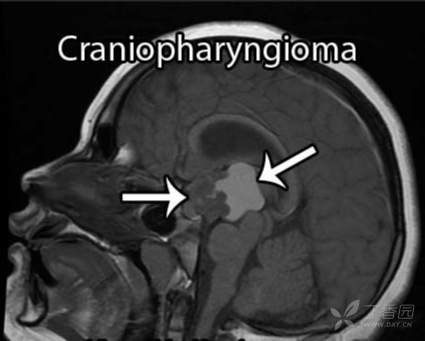

颅咽管瘤是一种良性肿瘤,虽然起源于垂体到下丘脑之间的很短一节垂体柄,但它能够生长成各种不同类型、质地、生长方向、各种各样的颅咽管瘤。不同解剖部位的颅咽管瘤可以是囊性的、实性的或囊实性的,还有部分肿瘤可能会存在一些钙化。它发生的主要部位在鞍区,也可以在鞍内、鞍上、鞍后、三脑室内部生长,可以侵袭到所有这些区域或部分这些区域。6-10岁儿童、26-30岁及41-45岁成人是颅咽管瘤的发病高峰年龄。男性一般多于女性。

颅咽管瘤可从垂体-下丘脑轴的任何一点发生并沿此轴发展,肿瘤可从位于蝶鞍到大脑的第三脑室,大约50%的肿瘤起源于第三脑室底水平的漏斗和/或灰结节区域,主要向第三脑室发展。 患者可出现头痛、视力损害和由中枢性尿崩症导致的多饮多尿等症状,儿童可出现发育迟缓,成人可出现性功能障碍和下丘脑综合征(如体温调节紊乱、水电平衡紊乱)。

颅咽管瘤病变的起源及部位决定它周围的重要解剖结构,包括视神经、垂体柄、下丘脑、还有颈内动脉的分支,基底动脉的分支,尤其基底动脉、后交通动脉和大脑后动脉跟肿瘤的关系可能会非常密切,此外还有脑干等。视神经跟视力有关系,垂体柄跟内分泌有关系,下丘脑决定病人认知能力和术后内分泌功能,脑干则是人体的“生命中枢”,颈内动脉、基底动脉这些大血管总管人体血液运输,手术切除过程中一旦损伤这些重要结构,可能导致灾难性、不可逆的神经功能损伤。

颅咽管瘤的手术治疗是现代神经外科挑战性的手术难题之一,这是因为肿瘤位置与下丘脑,垂体柄,视神经,视交叉和血管相毗邻,而正是这些决定了手术入路以及肿瘤切除的复杂性和术后并发症。目前用于鞍上区颅咽管瘤的开颅手术入路有额下入路、翼点入路、经胼胝体,或它们的组合入路。而在过去的几十年内,神经技术的极速发展使得神经内镜下经鼻蝶手术入路在神经外科领域占有了一席之地。对于鞍上颅咽管瘤,当前神经内镜经鼻蝶手术已成为传统开颅手术的替代方法,但目前文献中还缺乏有关生活质量和嗅觉功能等的相关数据。